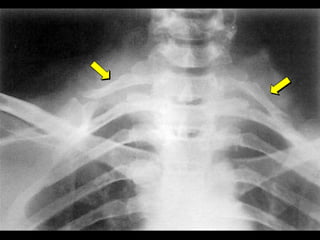

 Usually affects the aortic arch and its major

branches.

 The pulseles disease.

 Common in the far east.

 Severe forms can affect all the Aortic branches.

 Depostion of firm rubbery material in the

subintima. Autoimmune.

 Usually affectsthe aortic arch and its major branches.  The pulseles disease.  Common in the far east.  Severe forms can affect all the Aortic branches.  Depostion of firm rubbery material in the subintima. Autoimmune. WWW.SMSO.NET